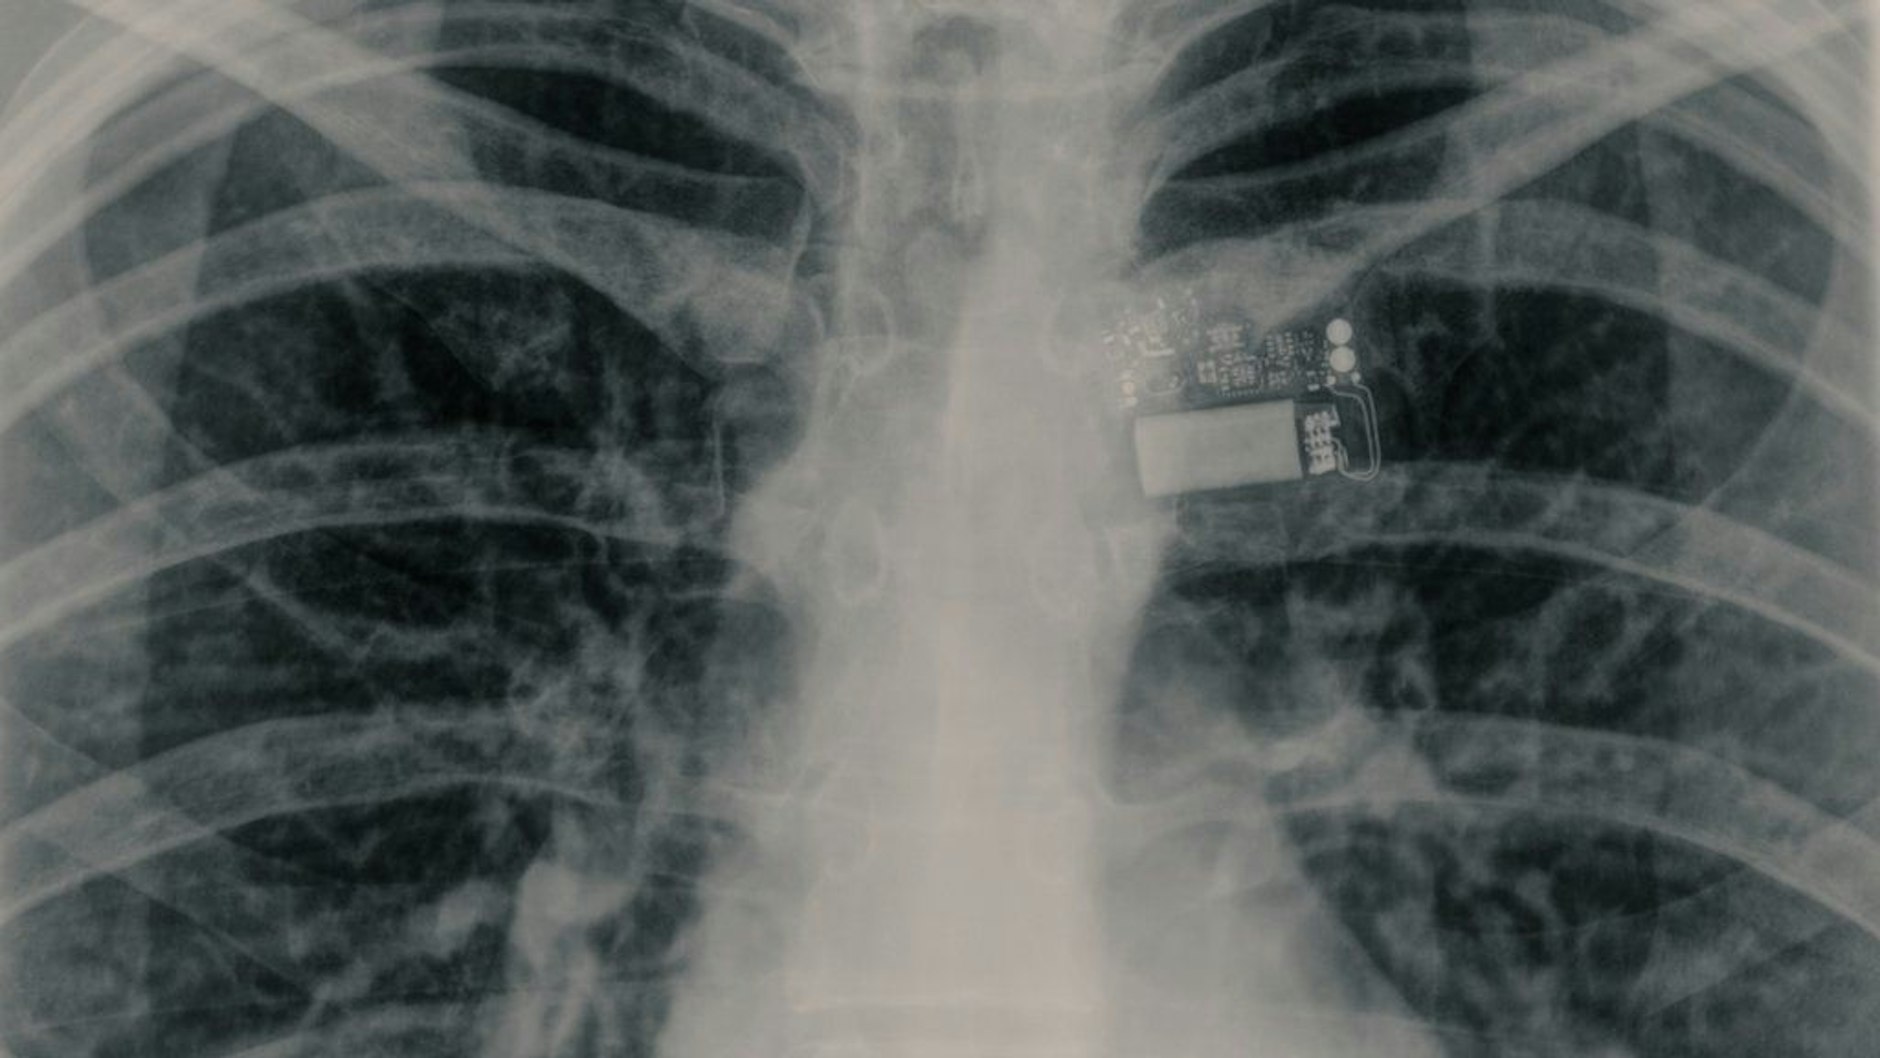

Derzeit werden aber erst einmal alle Experimente der Mission „Fram 2“ (benannt nach einem norwegischen Polarforschungsschiff aus dem 19. Jahrhundert) ausgewertet. Und diese galt nicht nur, die Polar-Regionen der Erde aus dem Weltall zu beobachten. Zu den Experimenten gehörte auch das Fertigen von Röntgen-Bildern. Auf der Erde ist das seit 1895 ein ganz gewöhnlicher Prozess. Aber im All wurde das noch nie gemacht.

Das erste Röntgenbild, das im Weltraum gemacht wurde: Rogge zeigt es uns auf ihrem Account des Nachrichtendienstes X. Zu sehen ist das Innerste eines der Crewmitglieder – der Brustkorb. Warum das etwas Besonderes ist?

Rogge schreibt: „Die Frage ist: Können wir im Weltraum qualitativ hochwertige Röntgenaufnahmen machen?“ Das sei sehr wichtig, herauszufinden, erklärt die Berlinerin. Denn: „Aufgrund von Knochenschwund in der Schwerelosigkeit können Frakturen auf Langzeitmissionen häufiger auftreten – daher benötigen wir eine Möglichkeit, diese zu diagnostizieren“, schreibt Rogge.

Und: „Röntgenaufnahmen können auch zur Untersuchung defekter Elektronik verwendet werden! Das witzigste Bild, das wir haben, ist eines, auf dem wir unseren Brustkorb und einen tragbaren Sensor aufgenommen haben. So haben wir beide Ziele gleichzeitig erreicht.“ Dieser Teil der Mission war also erfolgreich.